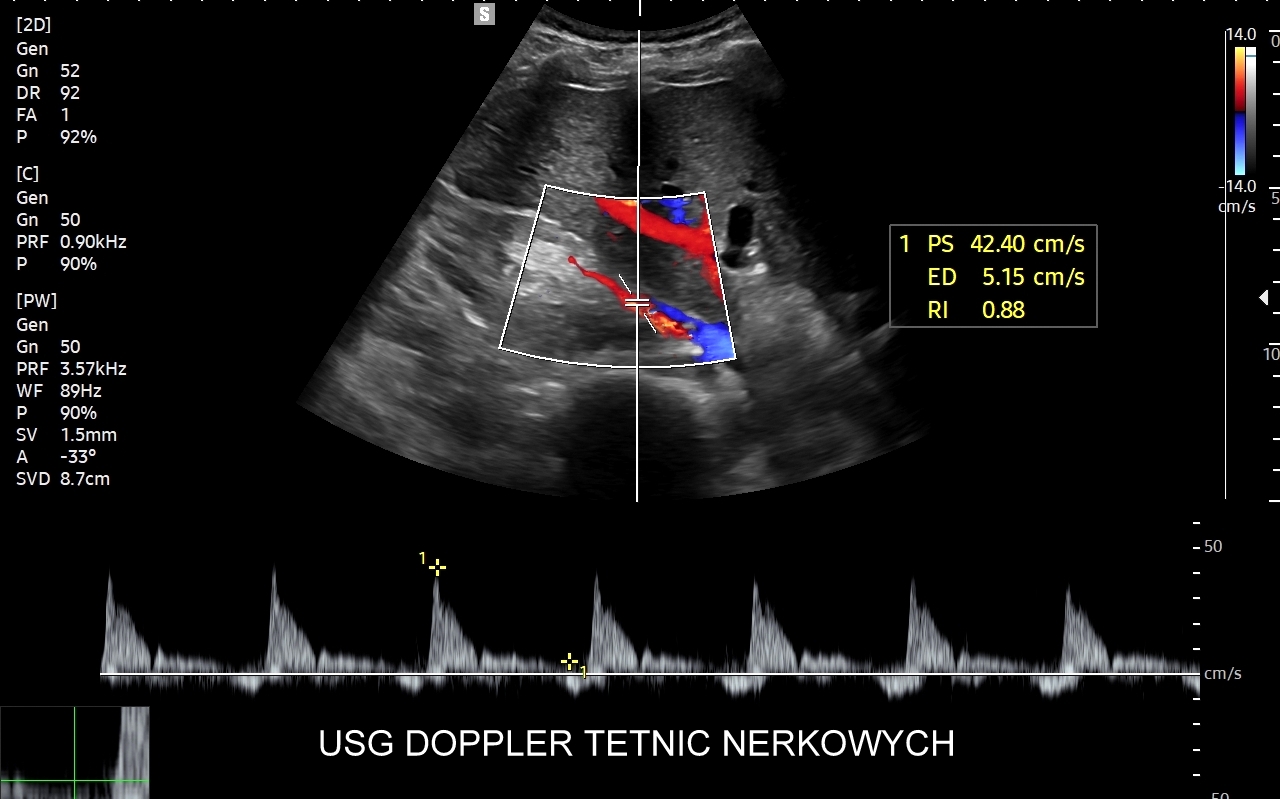

• w 2015 r. wprowadził do użycia badania dopplerowskie w diagnostyce cukrzycy i ocenie niewydolności nerek;

Dr Tomasz Szczepański posiada certyfikację Polskiego Towarzystwa Ultrasonograficznego w zakresie dopplerowskich badań naczyniowych. Każdego miesiąca przeprowadza nawet 350 badań naczyniowych | Pracownia USG Wrocław

• pełen przekrój badań dopplerowskich.

Dr Tomasz Szczepański zajmuje się kompleksową opieką medyczną nad swoimi Pacjentami. W ramach Interdyscyplinarnej Pracowni USG Wrocław wykonuje szereg uzupełniających się badań, zarówno klasycznych, jak USG jamy brzusznej, USG tarczycy, USG piersi, pełen zakres diagnostyki USG Doppler, jak i wysokospecjalistycznych, w tym badania multiparametryczne (MPUS), badania USG z kontrastem (CEUS), ocena przetok dializacyjnych, badania USG Doppler przepływów nerkowych, czy badania USG twarzy